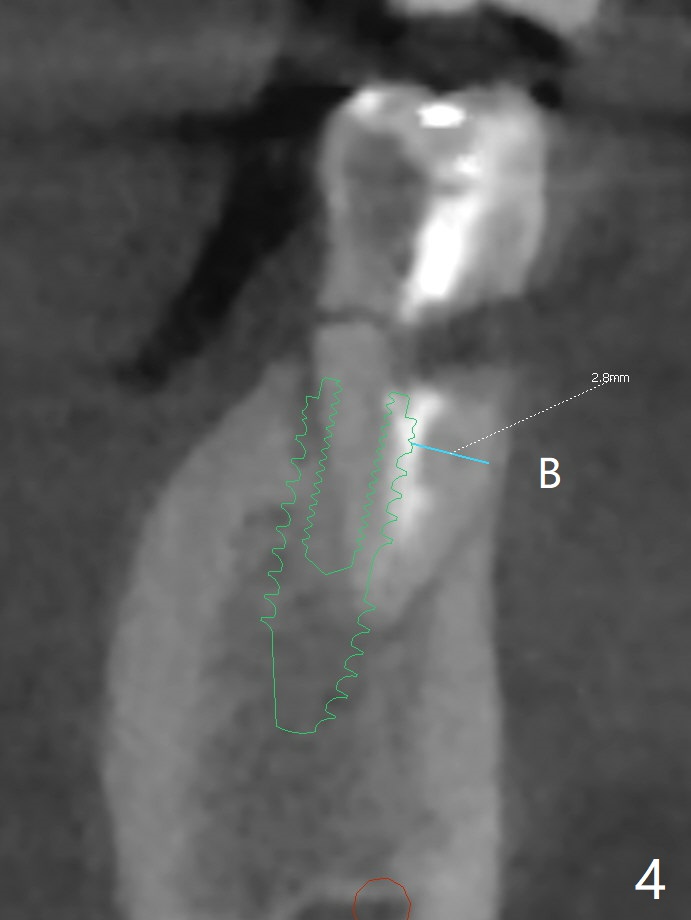

A 40-year-old man with #18 missing and #31 residual roots just fractures the tooth #20 (Fig.1). After discussion, he agrees to have implants at #18 and 20 first. To prevent buccal drifting of osteotomy and implant at #20, the implant will be placed lingual, but it does not contact the lingual plate (Fig.2-4). Traditionally, the whole tooth needs to be extracted (Fig.5,6) before initial osteotomy (Fig.7 red). The latter has tendency to drift buccal because of the lingual slope (Fig.7 arrow). To prevent the drifting, the crown of the tooth is removed (Fig.8). A guide is fabricated with 12 mm offset so that after bone trimmer (Fig.9 pink), the following drills have more contact with metal sleeve. Furthermore the drills will have less chance of buccal shifting because of the presence of the root.